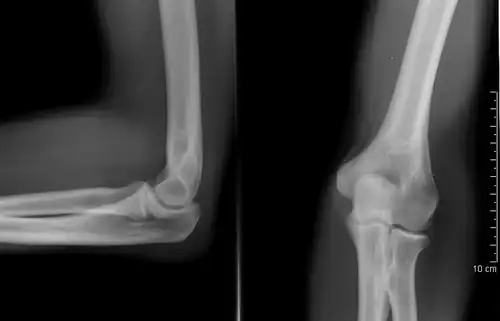

Left: Lateral X ray of a dislocated right elbow

Right: AP X ray of a dislocated right elbow

The types of disease most commonly seen at the elbow are due to injury.

X-ray of ventral dislocation of the radial head. There is calcification of annular ligament, which can be seen as early as 2 weeks after injury.[29]

Elbow dislocations constitute 10% to 25% of all injuries to the elbow. The elbow is one of the most commonly dislocated joints in the body, with an average annual incidence of acute dislocation of 6 per 100,000 persons.[30] Among injuries to the upper extremity, dislocation of the elbow is second only to a dislocated shoulder. A full dislocation of the elbow will require expert medical attention to re-align, and recovery can take approximately 6 weeks.